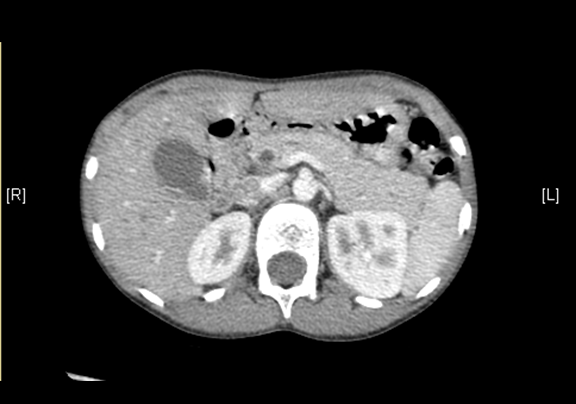

上腹部CT平扫:先天性胆管囊状扩张症并胆囊结石、胆囊炎症。

上腹部增强CT:肝总管-胆总管中上段梭形增宽,符合先天性胆管扩张所见(Ⅰ型)。

术前CT检查:

平衡期